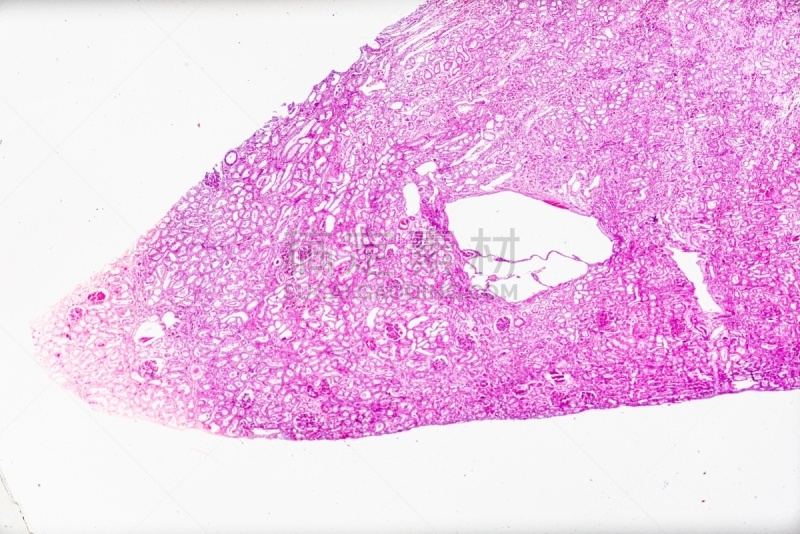

在显微镜下观察肝脏详情